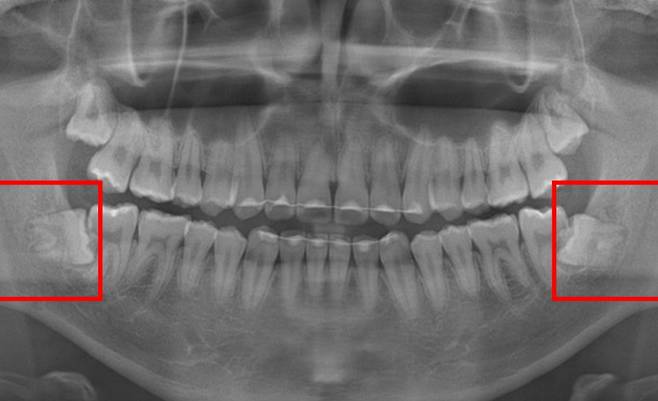

사랑니는 똑바로 자라지 않고 옆으로 비스듬히 나는 경우가 많다.

사랑니가 수평 방향으로 맹출하면 인접치 표면이 침식되는 치아 우식이나 치주염 등이 발생할 위험이 있으며, 치아 머리 주변으로 염증이 생기는 치관주위염의 원인이 되기도 한다.

이처럼 비스듬히 자란 사랑니는 주변 치아에도 영향을 미친다. 사랑니가 수평 방향으로 맹출하면 인접치 표면이 침식되는 치아 우식이나 치주염 등이 발생할 위험이 있으며, 치아 머리 주변으로 염증이 생기는 치관주위염의 원인이 되기도 한다. 치관주위염은 사랑니 주변 부기, 통증과 함께 개구(開口) 장애 등을 유발한다.